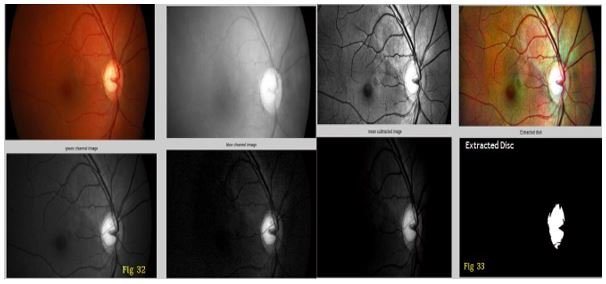

Optic cup segmented image

The cup is present inside the disk region. It was segmented by using morphological operations such as morphological opening, closing, dilation and erosion.

Figure 11: Determination of optic Cup.

In figure 11 a) we have find optic cup area size of retina is 796 mm.

Optic disk segmented image

• The optic disk is segmented by using Otsu thresholding

• Based on the thresholding level, the grayscale retina image was converted to black and white image in which, the centre portion, i.e. the optic disk alone will be in white color and the background will be in black

Figure 12: Determination of optic Disc.

Figure 12 we have find out area of optic Disc of retina which is 2346.

According to our condition if cup/disk < 0.4 then it is earlier stage glaucoma. Above figure cup to disk ratio is 0.3393 so above image is Normal eye image. In this patients image no Gluacoma symptom is found.

Figure 13: Window showing results of abnormal cup and Disk size.

Figure 13 shows MATLAB window showing results of abnormal cup and Disk size.